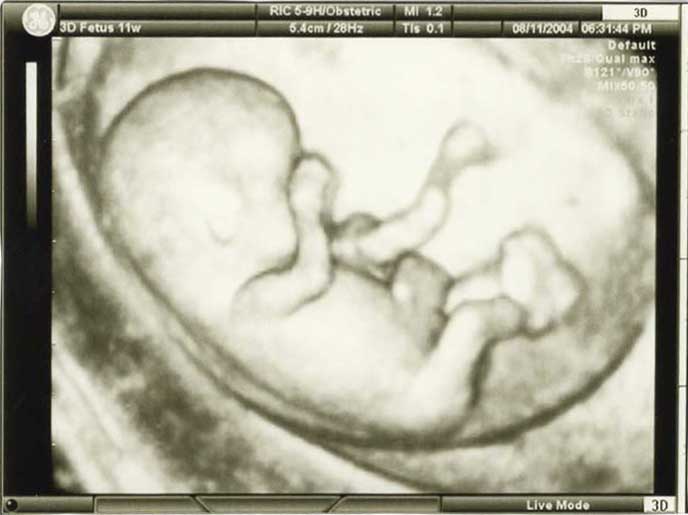

3D/4D HD LIVE

Στο ιατρείο μας προσφέρουμε υψηλής ευκρίνειας 3D και 4D τεχνολογία απεικόνισης του εμβρύου. Η τεχνολογία αυτή αποτελεί ένα ακόμα σημαντικό διαγνωστικό όπλο στη φαρέτρα του προγεννητικού ελέγχου, ενώ ταυτόχρονα ενισχύει την ανάπτυξη του δεσμού ανάμεσα στους μελλοντικούς γονείς και το μωρό τους.